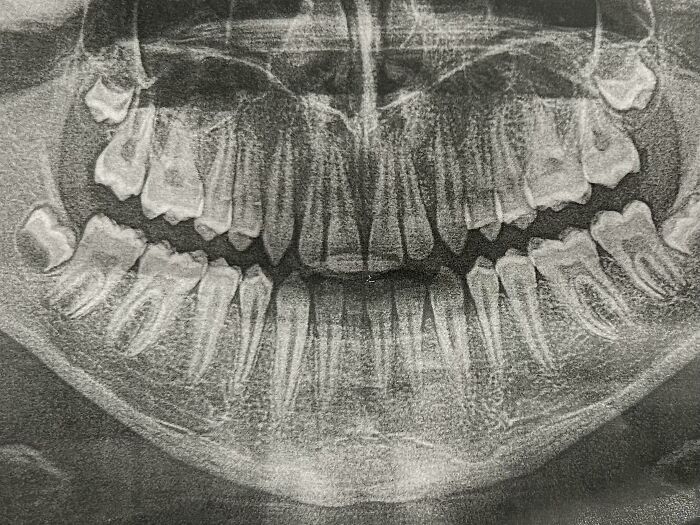

An X-Ray Of A Person Who Has 3 Full Sets Of Teeth